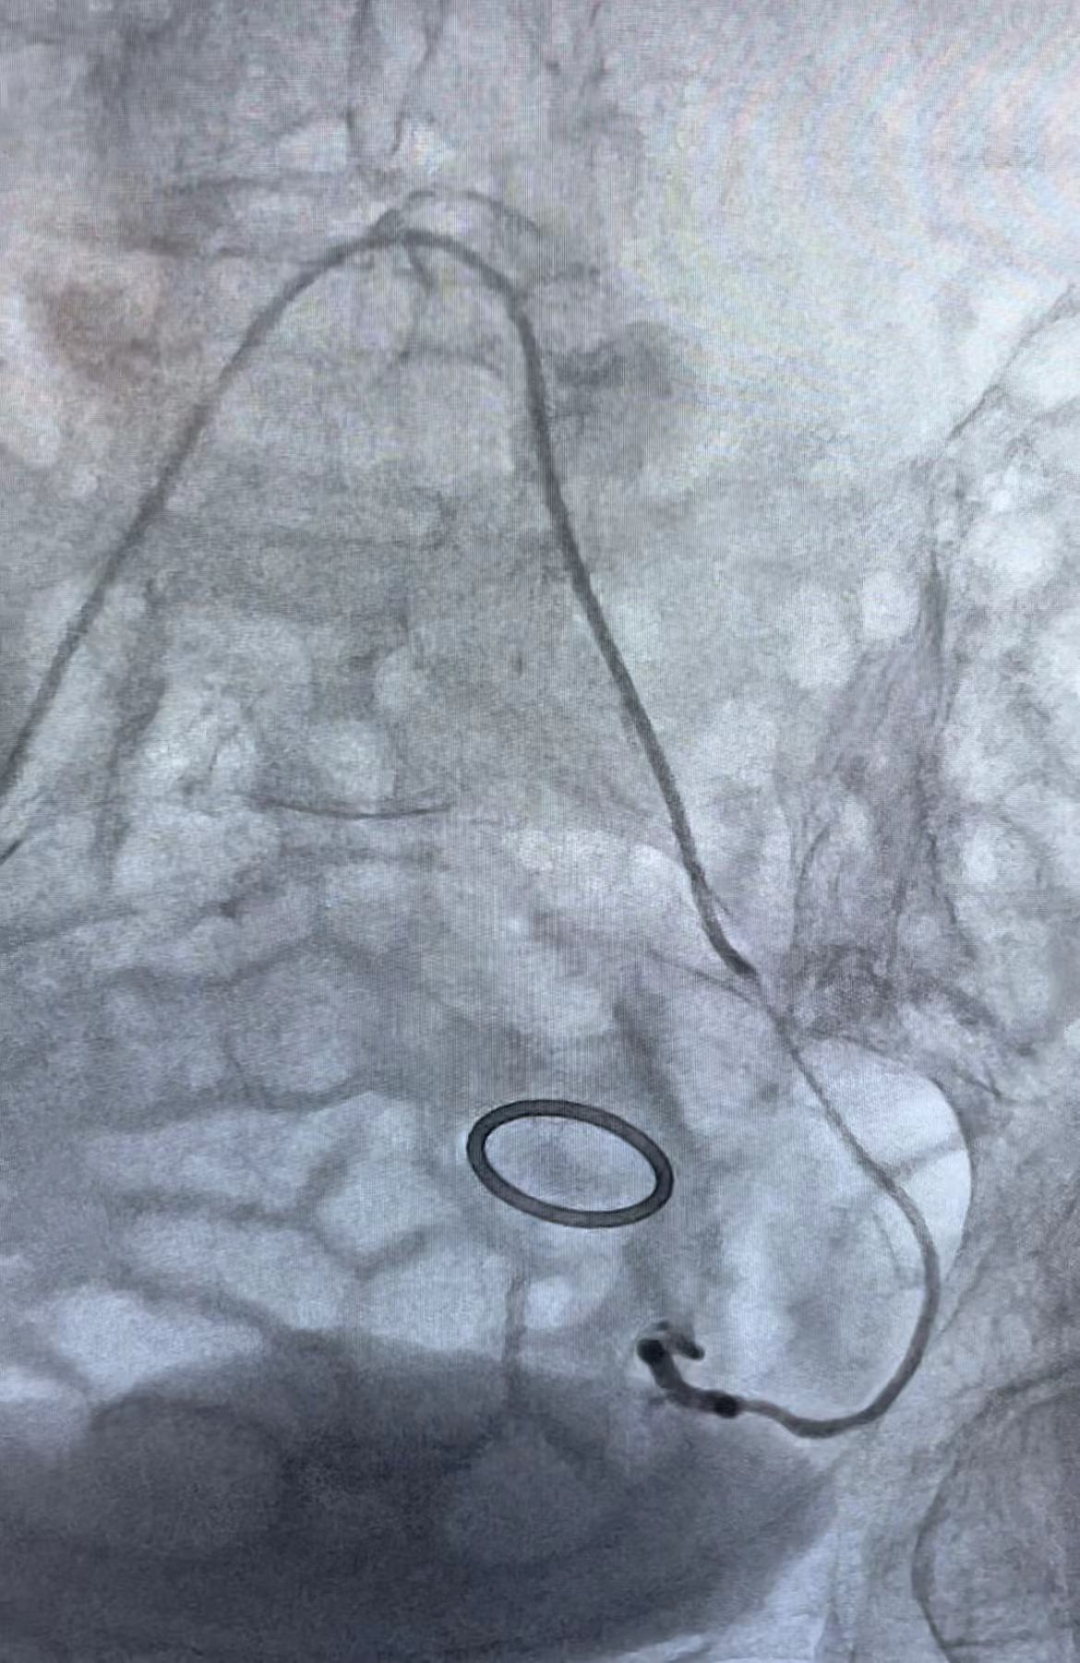

通过阴道填塞止血、药物止血,出血的问题解决得都不理想,肿瘤科马上参与到救治中来,肿瘤科鲍新医生会诊后评估,认为患者阴道流血时间长,同时,短期出血量进行性的增多引起了贫血并加重,考虑宫颈癌合并活动性出血,有大出血危及生命风险,有血管介入治疗止血指征,李岩与鲍新两位医生立即给患者施行了左右子宫动脉灌注化疗栓塞术,历时1小时,手术顺利完成。手术后,患者阴道流血明显减少,头晕和乏力的症状也明显缓解,可以安排后续的放化治疗方案。

栓塞前和栓塞后造影对比